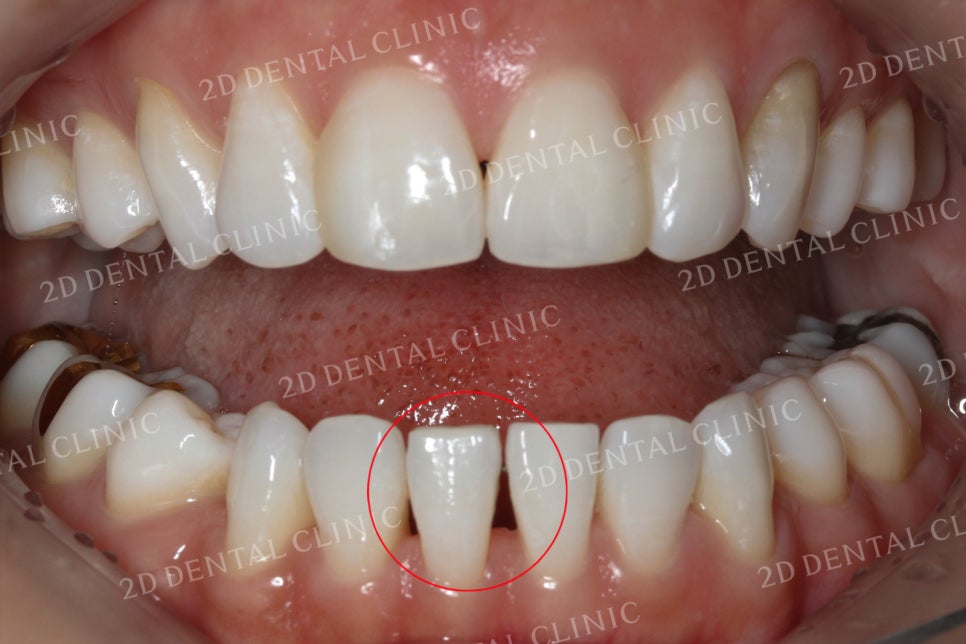

구강 개방 시 치아의 사진입니다.

표시된 부분에서 블랙트라이앵글이

확실하게 관찰되고 있네요.

이번 환자분께서는

상악 전치부의 6개 치아와

하악 전치부 6개 치아,

총 12개의 치아에 쎄라필름

시술을 진행하셨습니다.